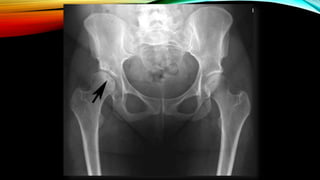

FILM: BOTH HIP AP

HOW TO DIAGNOSE AVN OF

FEMORAL HEAD?

• Radiograph (X-ray or MRI)

-Ficet and Arlet classification system